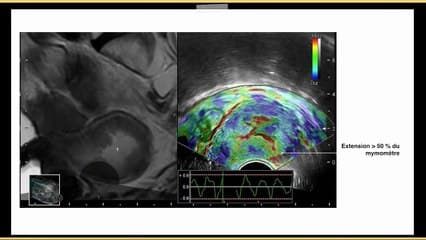

1 er résumé : L'auteur aborde les bases physiques et applications pratiques de l'IRM pour le coeur foetal. Les différentes séquences statiques et dynamiques sont décrites : L'apport actuel de l'IRM permet déjà de compléter l'échographie, par exemple pour certaines cardiopathies comme les tumeurs cardiaques,mais aussi pour évaluer un coeur qui est techniquement difficilement analysable en échographie. Les travaux de certaines équipes chevronnées en IRM sont décryptés. Les perspectives d'avenir sont le 3T, le STIC IRM, les simulations chirurgicales.2 ème résumé : Présentation didactique de l'IRM cardiaque suivie des indications en post-natal. En pré-natal la faisabilité y est abordée puis des cas pathologiques avec des séquences dynamiques. Ceci ouvre des perspectives dans le futur notamment en cas d'échographies difficiles à réaliser. Pour le moment méthode en cours d'évaluation.